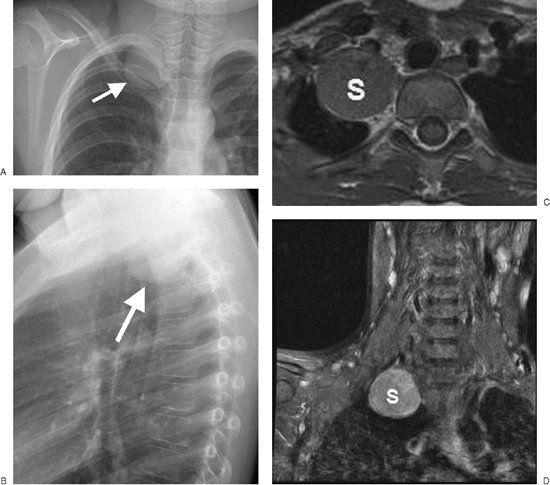

Neural tumors can be differentiated into nerve sheath tumors and ganglion cell tumors. Nerve sheath tumors comprise schwannomas, neurofibromas, and their malignant counterparts. The schwannoma is the most common intrathoracic

P.95

P.96

P.97

P.98

P.99

nerve sheath tumor (Fig. 6-39). Both schwannomas and neurofibromas are derived from Schwann cells and occur most commonly in patients in their 30s and 40s. Almost all intrathoracic nerve sheath tumors arise from either the intercostal or sympathetic nerves.

FIGURE 6-39. Benign schwannoma. PA (A) and lateral (B) chest radiographs of a 9-year-old girl show a circumscribed mass in the right apex (arrow). C: Axial T1-weighted MRI shows the mass (S) is paraspinal in location and has no continuity with the spinal canal. D: Coronal MRI, with intravenous contrast, shows that the mass (M) has high signal intensity.